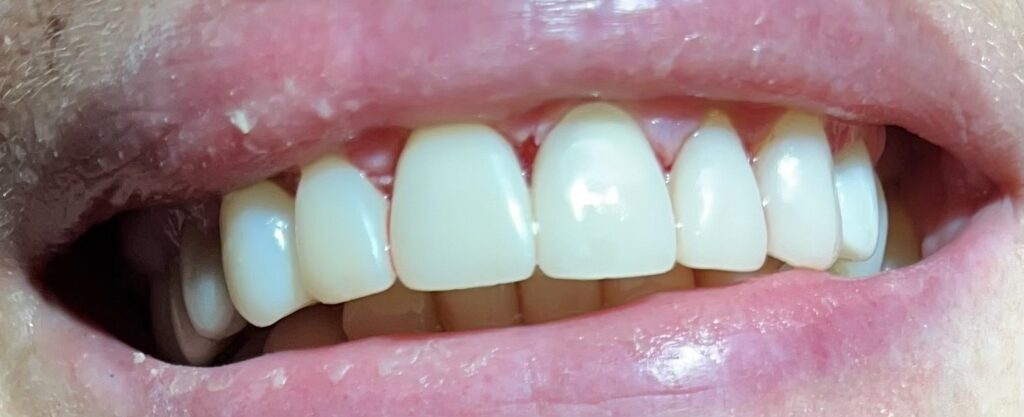

Każdy uśmiech ma swoją historię – my pomagamy ją opowiedzieć na nowo. Dzięki indywidualnie dobranym planom leczenia przywracamy pacjentom nie tylko piękny wygląd zębów, ale również komfort i funkcjonalność w codziennym życiu. Poniżej przedstawiamy wybrane przypadki metamorfoz, które pokazują, jak zaawansowana protetyka, nowoczesne techniki odbudowy oraz precyzyjne leczenie endodontyczne potrafią całkowicie odmienić uśmiech.